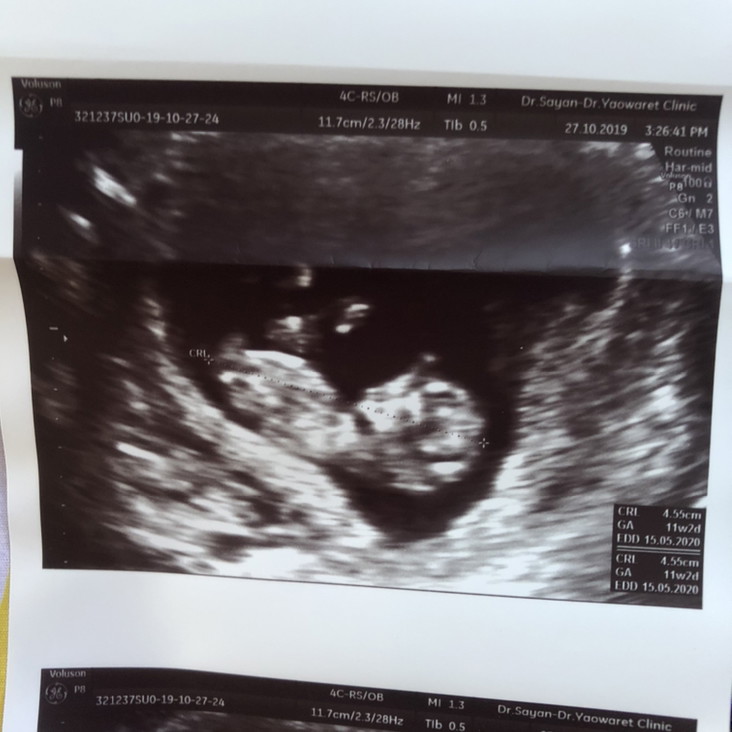

บ้านนี้ 11 สัปดาห์ จมูกแหลมๆค่ะ55

แม่ซาวกี่วิคคะ เห็นชัดมากค่ะ